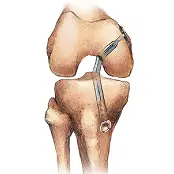

Knee Orthopedic Surgery